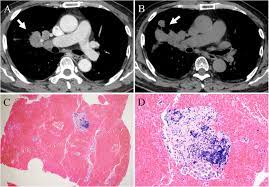

Can Lung Cancer Be Mistaken For Sarcoidosis - Case Report Pulmonary And Liver Sarcoidosis F1000research - Researchers emphasize that clinicians should be aware of systemic sarcoidosis because it can easily be mistaken for cancer progression.. Therefore we suggest that no lesion should be missed in these patients without biopsy by assuming lung involvement of sarcoidosis. Lung cancer should be excluded to confirm a diagnosis of sarcoidosis 4 , although the concurrence of sarcoidosis and lung cancer has been reported 5, 6, 7, 8 . Sarcoidosis patients may be misdiagnosed with tuberculosis, lymphoma, or lung cancer 4 . The standardized mortality rate for lung cancer was 3.26 (5.56 for males and 3.03 for females), indicating that sarcoidosis could be a risk factor for lung cancer. Various organs can be affected including the skin, lymph nodes, and liver.

When sarcoidosis affects the lungs, symptoms can mimic idiopathic pulmonary fibrosis including shortness of breath and a dry cough. Because both mesothelioma and sarcoidosis are hard to detect and present generalized chest and respiratory symptoms, the two conditions can be mistaken for one another. By definition, sarcoidosis is a systemic disease, affecting multiple organs in the body. If it is sarcoid, then you can get the help you need for this condition. There are currently no formal recommendations to guide the differential diagnosis workup between the evolution of lymphoma or a solid cancer and a granulomatous reaction associated with neoplasia. Since sarcoidosis and lung cancer can be present concurrently, performing biopsy to obtain pathology results from any suspected lung lesion in a patient diagnosed with sarcoidosis is essential. What every physician needs to know. Sarcoidosis is known to be a cancer mimicking and masking condition, it can follow cancer or develop concurrently with cancer, and significantly increased risk of cancer can affect sufferers of sarcoidosis.

That same fungal infection is often frequently mistaken for squamous cell carcinoma, or skin cancer, when it shows up on the skin. Sarcoidosis is a rare disease caused by inflammation. It usually occurs in the lungs and lymph nodes, but it can occur in almost any organ. Only 10 similar cases had been reported previously. When sarcoidosis affects the lungs, symptoms can mimic idiopathic pulmonary fibrosis including shortness of breath and a dry cough. No prior imaging was available for comparison. After some conversations and research i now know sarcoidosis can be mistaken for cancer. A condition called sarcoidosis, most commonly found in the lungs, can be mistaken for cancer, tuberculosis, or other infections, as its symptoms are similar. That time between when they tell you the possibilities and when you get the results from the biopsy is terrifying. Occasionally this pattern of fibrocystic change is seen in the lower lung zones, an atypical location that may cause pulmonary sarcoidosis to be mistaken for. Which was a flare up of sarcoidosis. A permanent pathological slide, however, indicated that right interlobar (#11s) lymph nodes involved both sarcoidosis and lung cancer metastasis. Can sarcoidosis turn into cancer.

Pancreatic cancer may be diagnosed as diabetes, due to the fact that diabetes is often a symptom or risk factor of pancreatic cancer. One report notes a case of systemic sarcoidosis that mimicked the symptoms and metastatic spread of cancer. Since sarcoidosis and lung cancer can be present concurrently, performing biopsy to obtain pathology results from any suspected lung lesion in a patient diagnosed with sarcoidosis is essential. When referring to the stages of sarcoidosis, this is referring exclusively to pulmonary sarcoidosis. Sarcoidosis is known to be a cancer mimicking and masking condition, it can follow cancer or develop concurrently with cancer, and significantly increased risk of cancer can affect sufferers of sarcoidosis. Although it is most commonly thought to be a lung disease, sarcoidosis has been shown to affect almost any organ. There are currently no formal recommendations to guide the differential diagnosis workup between the evolution of lymphoma or a solid cancer and a granulomatous reaction associated with neoplasia. Apparently, lymphomas can sometimes harbor sarcoidal granulomas within cancer — and this change, although rare, is thought to perhaps reflect an immune reaction to the cancer tumor, and not the systemic disease, sarcoidosis.

Pancreatic cancer may also be misdiagnosed as gallstones or pancreatitis, or the inflammation of the pancreas. After some conversations and research i now know sarcoidosis can be mistaken for cancer. A condition called sarcoidosis, most commonly found in the lungs, can be mistaken for cancer, tuberculosis, or other infections, as its symptoms are similar. I've been going to support groups for the disease for 20 years now and find 3 or 4 patients a year who are diagnosed initially as having lung cancer. That same fungal infection is often frequently mistaken for squamous cell carcinoma, or skin cancer, when it shows up on the skin. Sarcoidosis can also affect calcium metabolism, the nervous system, the liver and spleen, muscles, bones and joints, the kidneys, lymph nodes, or any other organ. Various organs can be affected including the skin, lymph nodes, and liver. Sarcoidosis and neoplasia, especially lymphoma, can show overlapping presentations, thus making the diagnosis and treatment harder to deal with. Copd is a term used for a group of obstructive lung diseases. There are currently no formal recommendations to guide the differential diagnosis workup between the evolution of lymphoma or a solid cancer and a granulomatous reaction associated with neoplasia. Since sarcoidosis and lung cancer can be present concurrently, performing biopsy to obtain pathology results from any suspected lung lesion in a patient diagnosed with sarcoidosis is essential. Despite careful preparation, it thus remains difficult to distinguish between these conditions even when lymph nodes are strictly evaluated. Only 10 similar cases had been reported previously.